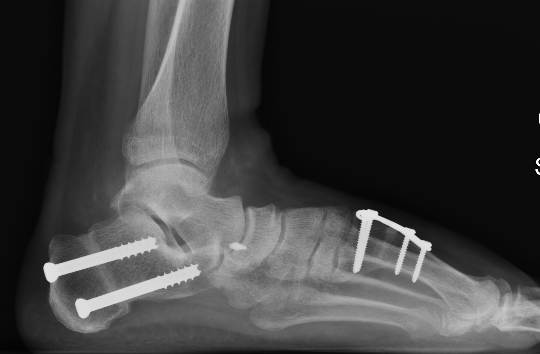

Medial displacement calcaneal osteotomy

Technique

Lateral approach

- curve just below peroneals

- protect sural nerve branches

- homann superiorly in front of tendoachilles

- homann inferiorly under calcaneum

Oblique osteotomy behind posterior facet

- 45o cut with saw

- open with lamina spreader

- split periosteum medially with osteotome

- avoid damage to medial structures

- transfer medially 1 cm

- screw fixation